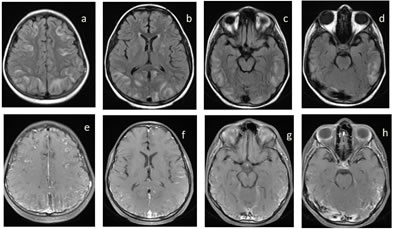

Figure 4: Posterior reversible encephalopathy syndrome (PRES) in a k/c/o ALL, post chemotherapy (L-asparginase) now c/o seizures. (a,b,c,d) FLAIR images showing vasogenic edema in bilateral frontal, parietal, temporal nad occipital lobes. (e,f,g,h) Post contrast T1 images showing leptomeningeal enhancement and patchy cortical enhancement in the involved areas.